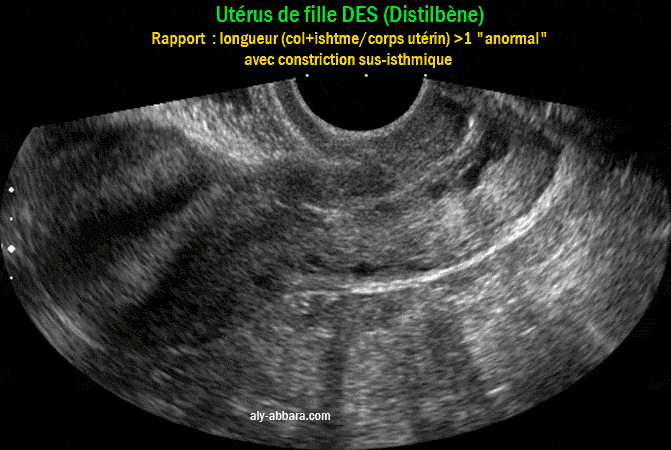

Utérus d'une fille DES présentant un prolongement inhabituel de la portion supra-vaginale du col utérin avec un rapport de la longueur du col et l'isthme utérin (45mm) par rapport à la longueur du corps utérin (40mm), c'est-à-dire un coprs utérin proportionnellement court

• Utérus d'une femme de 36 ans, fille DES ; il présente :

• un prolongement inhabituel de la portion supra-vaginale du col utérin (col+isthme = 45mm) ;

• raccourcissement relatif de la longueur du corps utérin (40mm) comparée à la longueur du col et l'isthme utérins ;

• rapport : longueur (col + isthme) /longueur du corps utérin = environ 1 ;

• (normalement, chez la femme adulte, ce rapport est égale à (1/2)

• une constriction au niveau de la région sus-isthmique.

• Remarque : il s'agit d'une femme ayant déjà mis au monde un enfant de 3200.g à 37 SA.